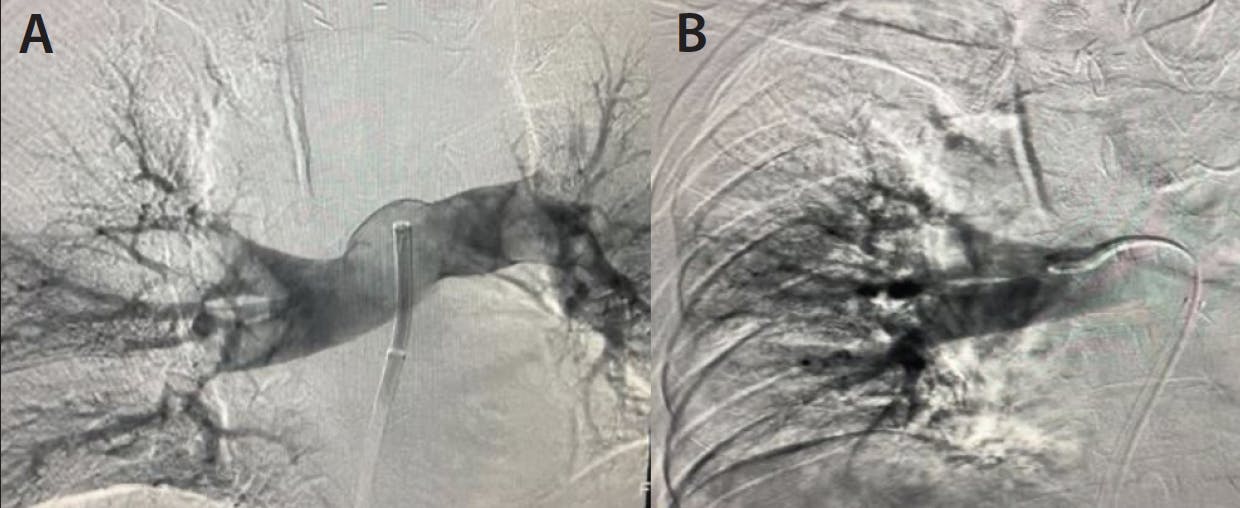

PROCEDURAL DETAILS

After access was gained in the groin, pressures were taken in the main PA showing a preprocedural reading of 29/9 mm Hg (mean, 16 mm Hg). Lightning Flash was then introduced into the vasculature and navigated into the main PA. With the catheter at the face of thrombus, aspiration was initiated. The Lightning Flash catheter was then torqued to engage thrombus in both the right and left PA to remove the bilateral clot burden (Figure 1). Once the thrombus was sufficiently addressed, angiograms were obtained and pressures were taken for further confirmation (Figures 2A and 2B), showing great improvement at 21/4 mm Hg (mean, 10 mm Hg).

Figure 1. Clot burden removed.

Figure 2. Preprocedural angiogram of the main PA (A) and postthrombectomy angiogram of the right PA (B).

CONCLUSION

After the procedure, the patient was taken to the intensive care unit where his oxygen requirement immediately improved. By the next morning, the patient was taken off nasal cannula and stated that they had no difficulty breathing room air. The patient was discharged from the intensive care unit the following day. MUSC’s PERT (PE response team) was able to work as a cohesive unit to provide treatment for a patient with an emergent condition during an overnight shift. Lightning Flash allowed this team the ability to provide immediate treatment for rapid thrombus removal in a situation that demanded it.